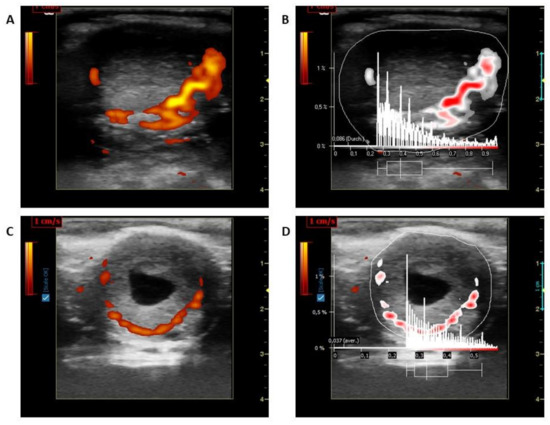

LBF of the CL was measured using a Color Doppler (portable LOGIQ Book XP ultrasound device-General Electrics Healthcare, Solingen, Germany; 10 MHz linear probe- Model 1739RS, Tokyo, Japan). Ultrasonographic controls and pictures taken were processed as described previously [14,15]. Pictures were frozen at the maximum cross-section and saved for measurements. The pictures were then examined using the same instrument equipped with a linear probe for imaging BF of CL in power Doppler mode (Doppler frequency: 5 MHz; gain: 19.5; pulse repetition frequency: 0.5 kHz). Five pictures without flash artefacts and a maximum number of colored areas were stored in system memory in the DICOM (Digital Imaging and Communications in Medicine) format. The stored Doppler images (5 images of blood flow regions in the LC) were analyzed using a specialised software program (Pixel Flux, version 1.0, Chameleon Software, Leipzig, Germany). For this, the entire CL structure and blood flow region was selected as the regions of interest and the colored areas were calculated (Figure 1). An average of five images was used to evaluate LBF further.

Figure 1. (A) Corpus luteum blood flow in CP; (B) Evaluation of Corpus luteum using Pixelflux program of Figure 1A; (C) Corpus luteum blood flow in HP; (D) Evaluation of Corpus luteum using Pixelflux program of Figure 1C.